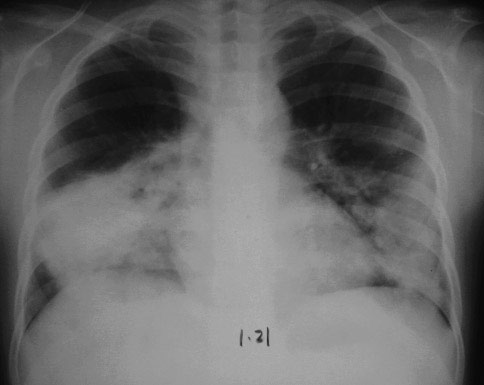

肺炎检查报告

肺炎检查报告,